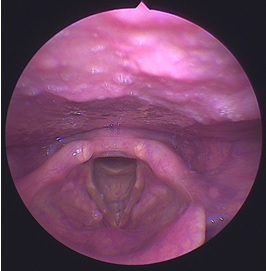

這是一個聲帶結繭的病人,可以看到在兩側聲帶上有栗狀般的小結節,聲帶結繭是因為長期聲帶過度使用所造成,輕微早期的聲帶結繭藥物治療部份還有不錯的療效,對於治療效果不滿意或是嚴重的患者,則需要手術治療,所以提早治療,平常不要濫用聲音,才能擁有一個健康的聲帶。